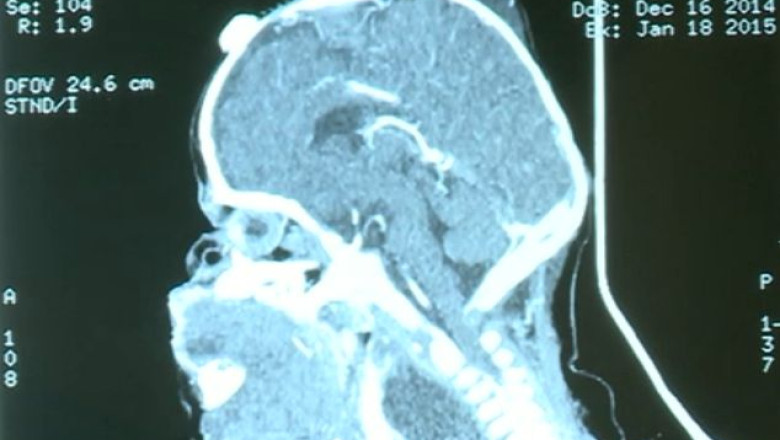

Casiana s-a născut la jumătatea lunii trecute, la Feteşti. Este al cincilea copil al familiei, dar bucuria părinţilor s-a transformat repede în îngrijorare. Fetiţa a venit pe lume cu o tumoră gigant, care nu a fost descoperită la controalele din timpul sarcinii.

Imediat după naştere, Casiana a fost trimisă de urgenţă la Spitalul Marie Curie din Bucureşti. Deşi nu mai văzuseră un caz atât de grav, medicii au decis să o opereze. Era singura şansă a fetiţei. Au cerut ajutorul specialiştilor din Statele Unite ale Americii, care au răspuns imediat apelului. Intervenţia chirurgicală, care s-a făcut pentru prima dată în România, a durat opt ore şi a fost un succes. Medicii au reuşit să extirpe tumora care o sufoca pe copilă.